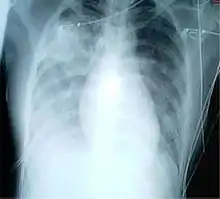

Un caso probable se define como un caso sospechoso con el hallazgo adicional de neumonía o síndrome respiratorio por radiografía de tórax o autopsia.